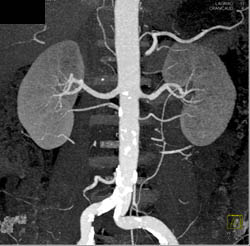

1 Cm Renal Cell Carcinoma